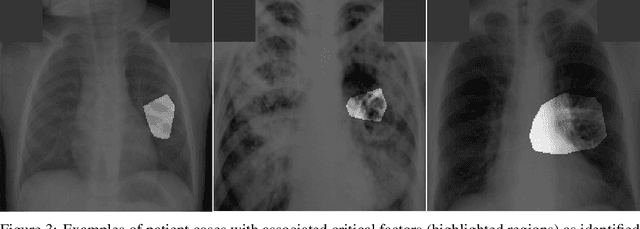

Abstract:Tuberculosis (TB) remains a global health problem, and is the leading cause of death from an infectious disease. A crucial step in the treatment of tuberculosis is screening high risk populations and the early detection of the disease, with chest x-ray (CXR) imaging being the most widely-used imaging modality. As such, there has been significant recent interest in artificial intelligence-based TB screening solutions for use in resource-limited scenarios where there is a lack of trained healthcare workers with expertise in CXR interpretation. Motivated by this pressing need and the recent recommendation by the World Health Organization (WHO) for the use of computer-aided diagnosis of TB, we introduce TB-Net, a self-attention deep convolutional neural network tailored for TB case screening. More specifically, we leveraged machine-driven design exploration to build a highly customized deep neural network architecture with attention condensers. We conducted an explainability-driven performance validation process to validate TB-Net's decision-making behaviour. Experiments on CXR data from a multi-national patient cohort showed that the proposed TB-Net is able to achieve accuracy/sensitivity/specificity of 99.86%/100.0%/99.71%. Radiologist validation was conducted on select cases by two board-certified radiologists with over 10 and 19 years of experience, respectively, and showed consistency between radiologist interpretation and critical factors leveraged by TB-Net for TB case detection for the case where radiologists identified anomalies. While not a production-ready solution, we hope that the open-source release of TB-Net as part of the COVID-Net initiative will support researchers, clinicians, and citizen data scientists in advancing this field in the fight against this global public health crisis.